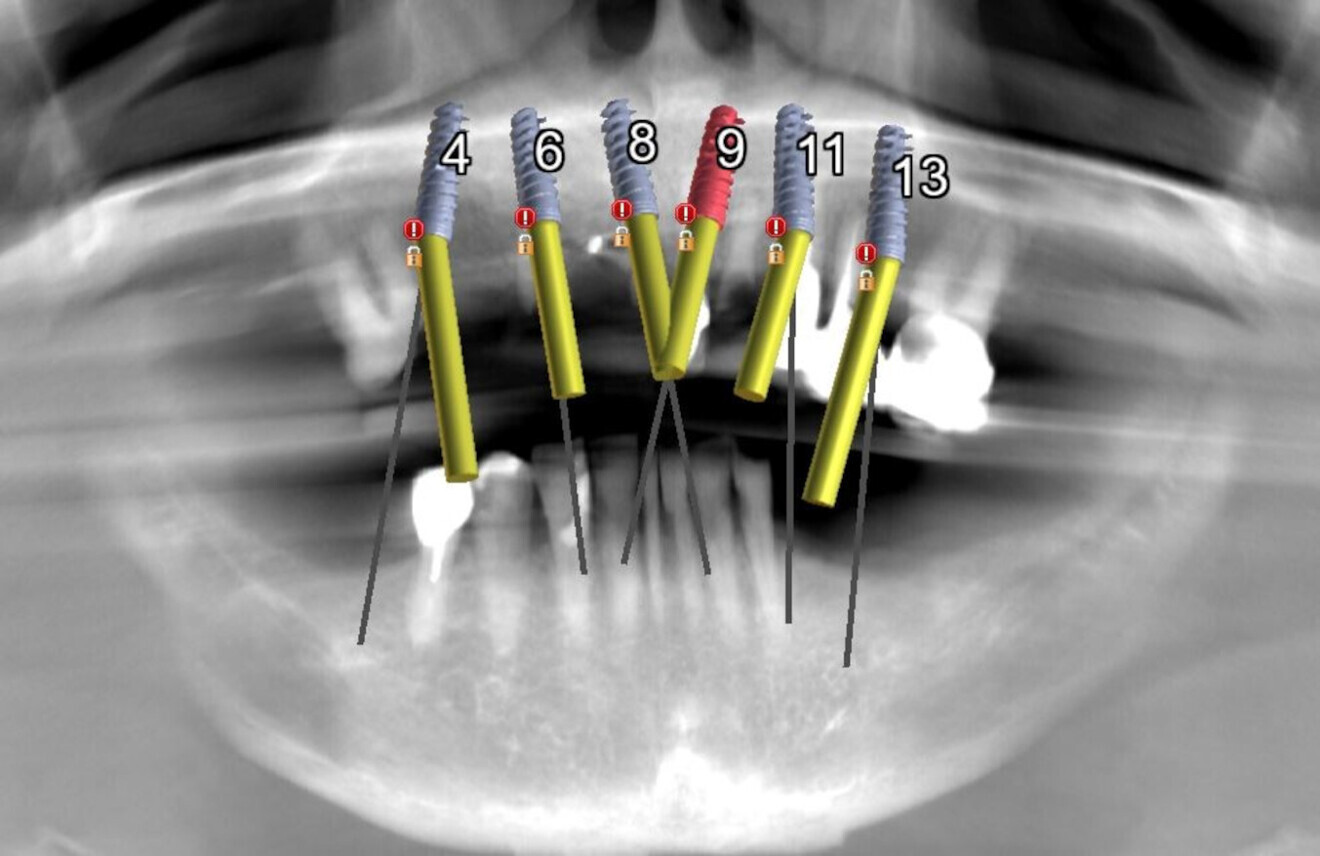

The planning continued with the examination and manipulation of the 3D reconstructed volume of the mandible and maxilla (Fig. 6a). Using the isolate function within the Blue Sky Plan software, the mandibular arch was separated from the maxillary arch, which with the merging of the intra-oral scanning data helped with the restoratively driven planning and refinement of implant positioning (Figs. 6b & c). The implants were then planned with precise regard for the emergence of the screw access channels represented by the yellow abutment projections which extended above the occlusal plane (Fig. 6d). Once each of the implant receptor sites and the vertical positions had been validated, the amount of alveolar reduction (after tooth extraction) was determined. A bone reduction guide was then designed with four anchor pins for stable fixation to the mandible (Fig. 7a). The various components of the diagnostic progress can be better appreciated using selective transparency to visualise structures based on their density (Fig. 7b). Selective transparency was again utilised to visualise the final location of the three central straight implants and the two angled implants, clearly indicating the safe proximity to the bilateral inferior alveolar nerves (Fig. 8a). The translucent STL model of the mandibular teeth and virtual teeth helped relate the implant positions to the restorative plan (Fig. 8b). The sequential osteotomy drilling guide was designed based upon the parameters of the implant system and guided drilling kit utilised. The osteotomy drilling guide was to be secured to the mandible with the same fixation pins as used for the bone reduction guide (Fig. 9).

Therefore, the maxillary implants were buried in a two-stage protocol. To preserve the width and height of the residual alveolar ridge, the extraction sites were all filled with the grafting material gleaned from the teeth extracted from the mandibular arch (Fig. 19a) and covered with large 20 × 30 mm collagen membranes (Fig. 19b). The immediate postoperative panoramic radiograph showed the placement of five implants for the mandibular arch and six for the maxillary arch (Fig. 20). The classic radiolucent appearance of fresh extraction sites was not evident, as each had been filled with the dentine grafting material. Small, round radiolucent holes could be visualised in the mandibular arch from the four fixation screws. The 2D panoramic reconstructed view is somewhat distorted and thus the true trajectory of each implant cannot be accurately appreciated. It was the original plan that the right and left most distal tilted implants would receive 30° angulated multi-unit abutments at the appropriate tissue cuff height once the implants had been uncovered and after osseointegration had been confirmed.